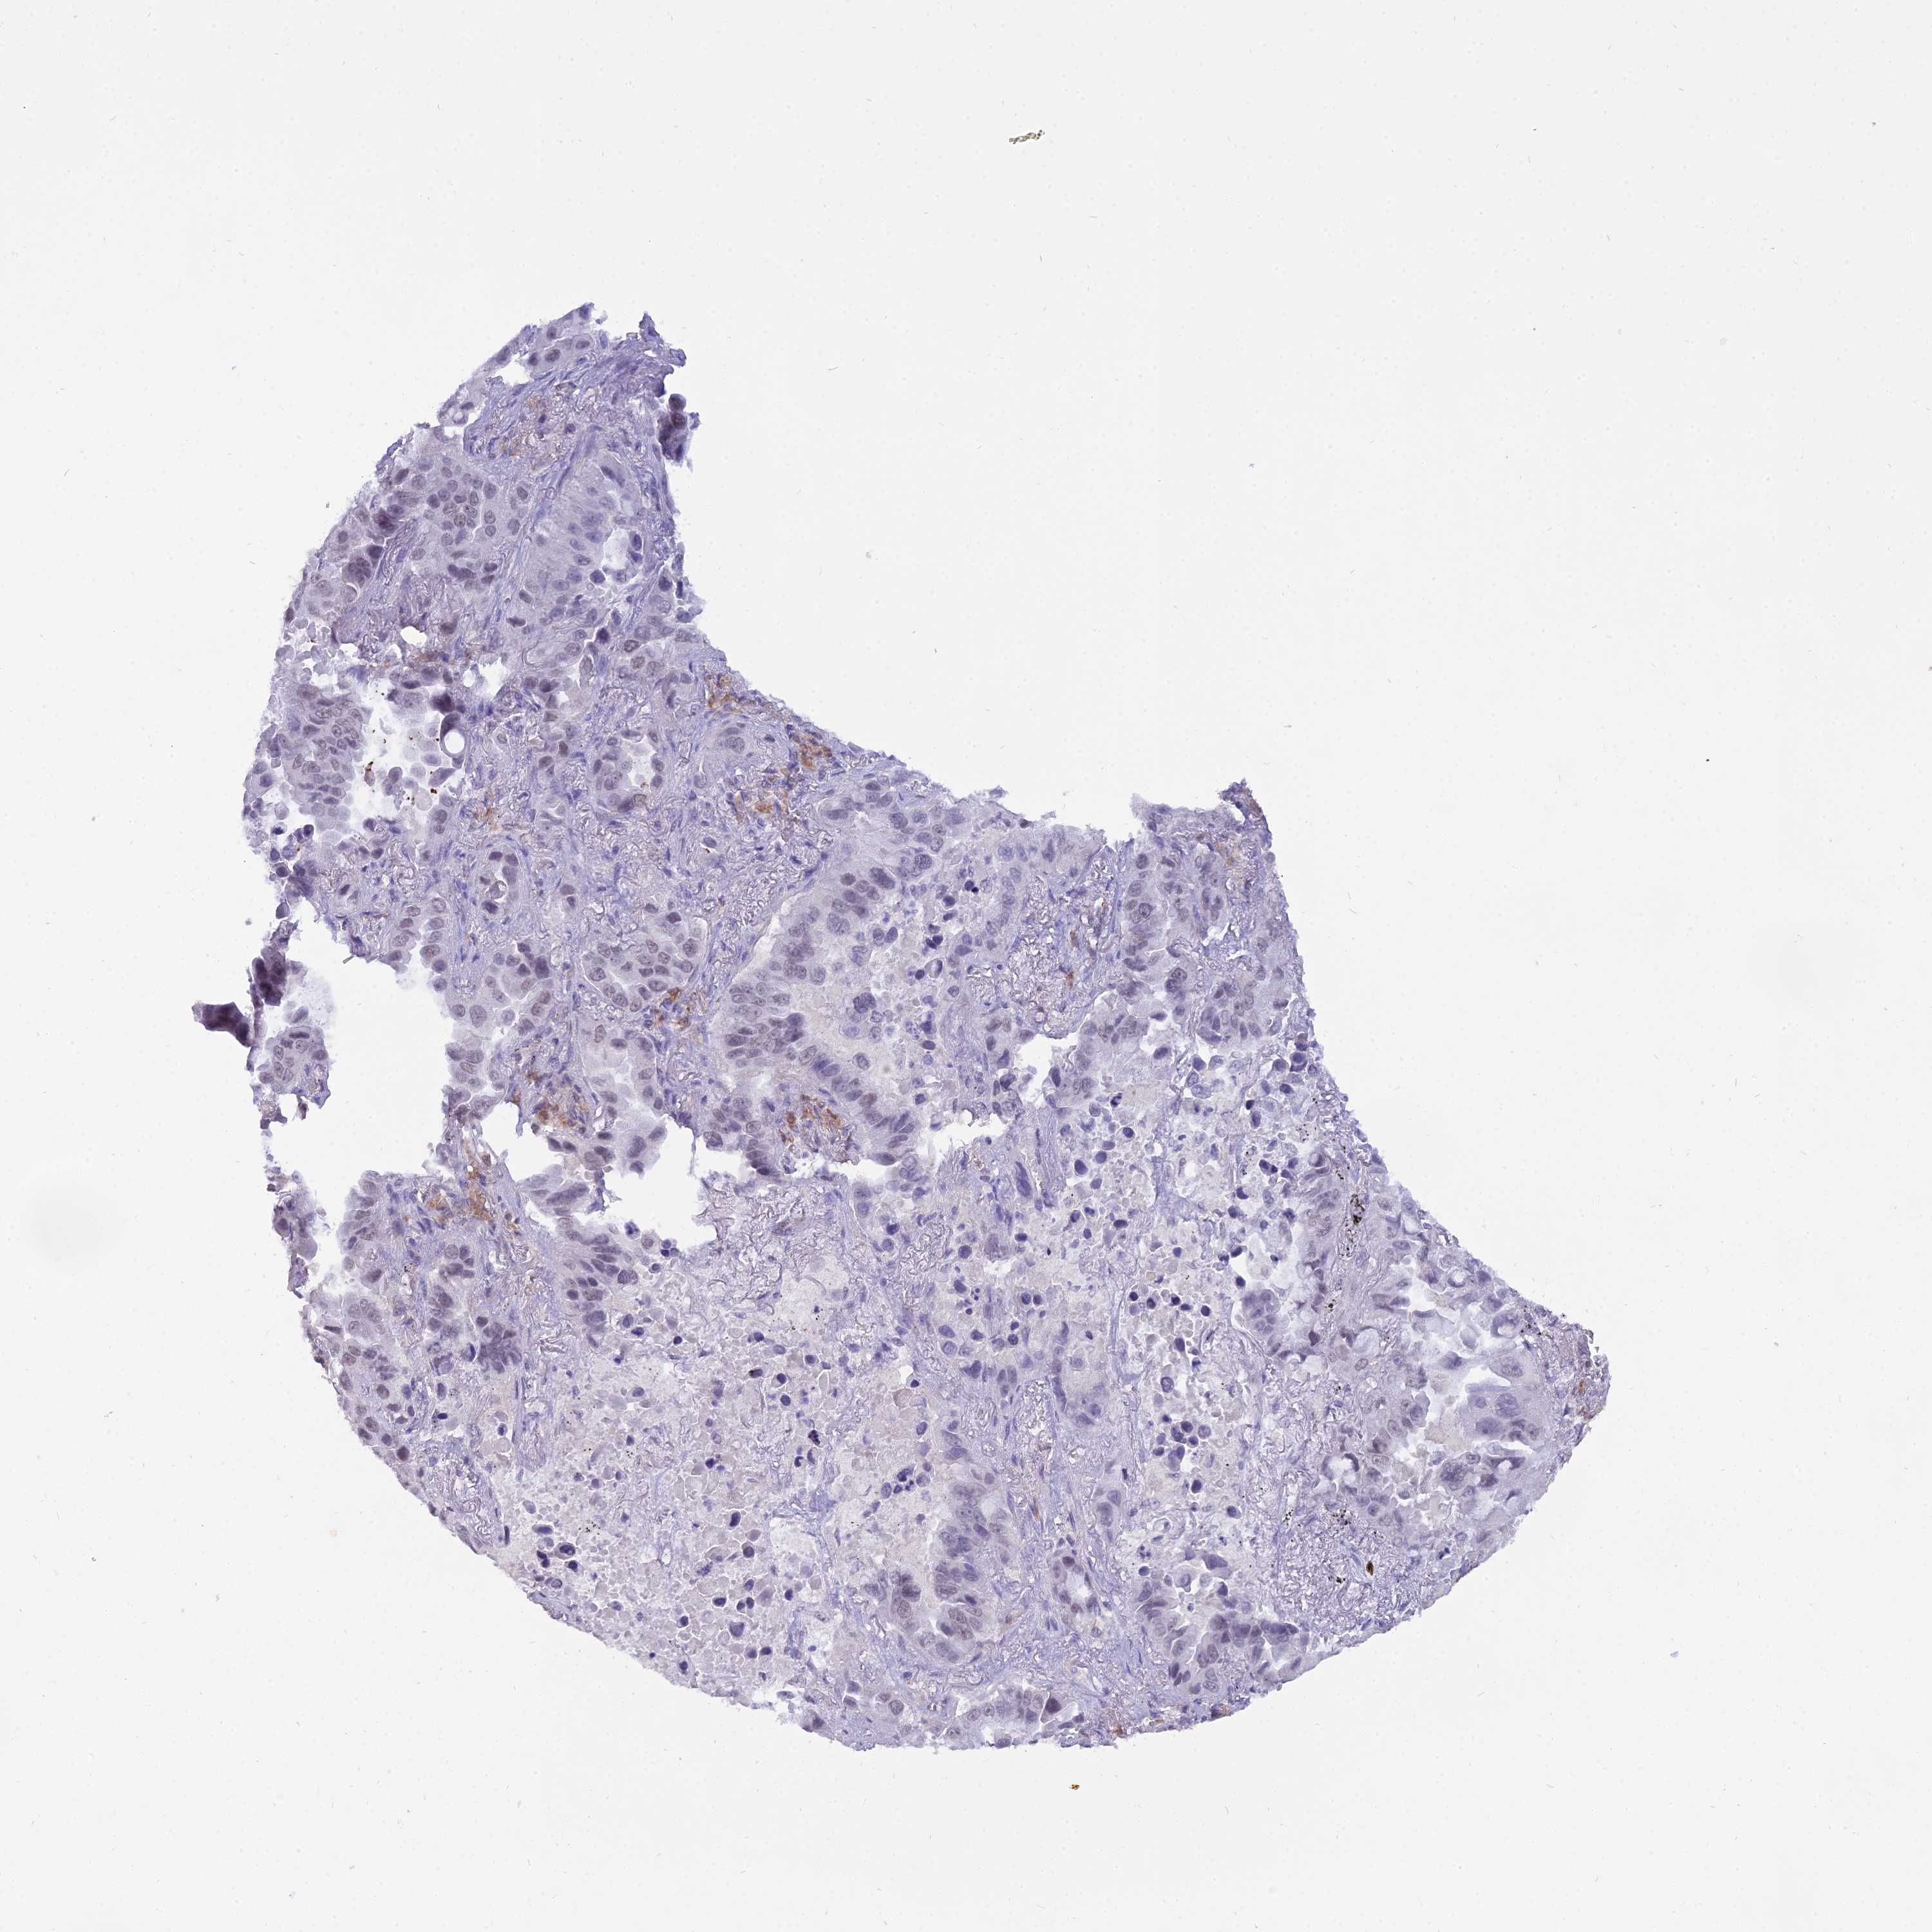

CANCER LUNG CANCER Show tissue menu

LUAD TCGA LUAD VALIDATION LUSC TCGA LUSC VALIDATION PROTEIN LUAD CPTAC PROTEIN LUSC CPTAC PROTEIN EXPRESSION